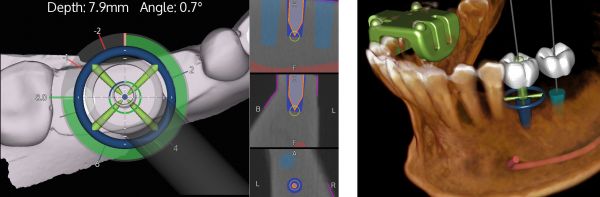

Calibration In Dynamic Navigation Surgery In Implamt

Browse our specialized Calibration In Dynamic Navigation Surgery In Implamt portfolio with numerous expertly curated photographs. optimized for both digital and print applications across multiple platforms. providing reliable visual resources for business and academic use. Each Calibration In Dynamic Navigation Surgery In Implamt image is carefully selected for superior visual impact and professional quality. Perfect for marketing materials, corporate presentations, advertising campaigns, and professional publications All Calibration In Dynamic Navigation Surgery In Implamt images are available in high resolution with professional-grade quality, optimized for both digital and print applications, and include comprehensive metadata for easy organization and usage. Our Calibration In Dynamic Navigation Surgery In Implamt collection provides reliable visual resources for business presentations and marketing materials. Whether for commercial projects or personal use, our Calibration In Dynamic Navigation Surgery In Implamt collection delivers consistent excellence. The Calibration In Dynamic Navigation Surgery In Implamt archive serves professionals, educators, and creatives across diverse industries. Regular updates keep the Calibration In Dynamic Navigation Surgery In Implamt collection current with contemporary trends and styles. Advanced search capabilities make finding the perfect Calibration In Dynamic Navigation Surgery In Implamt image effortless and efficient. Multiple resolution options ensure optimal performance across different platforms and applications.